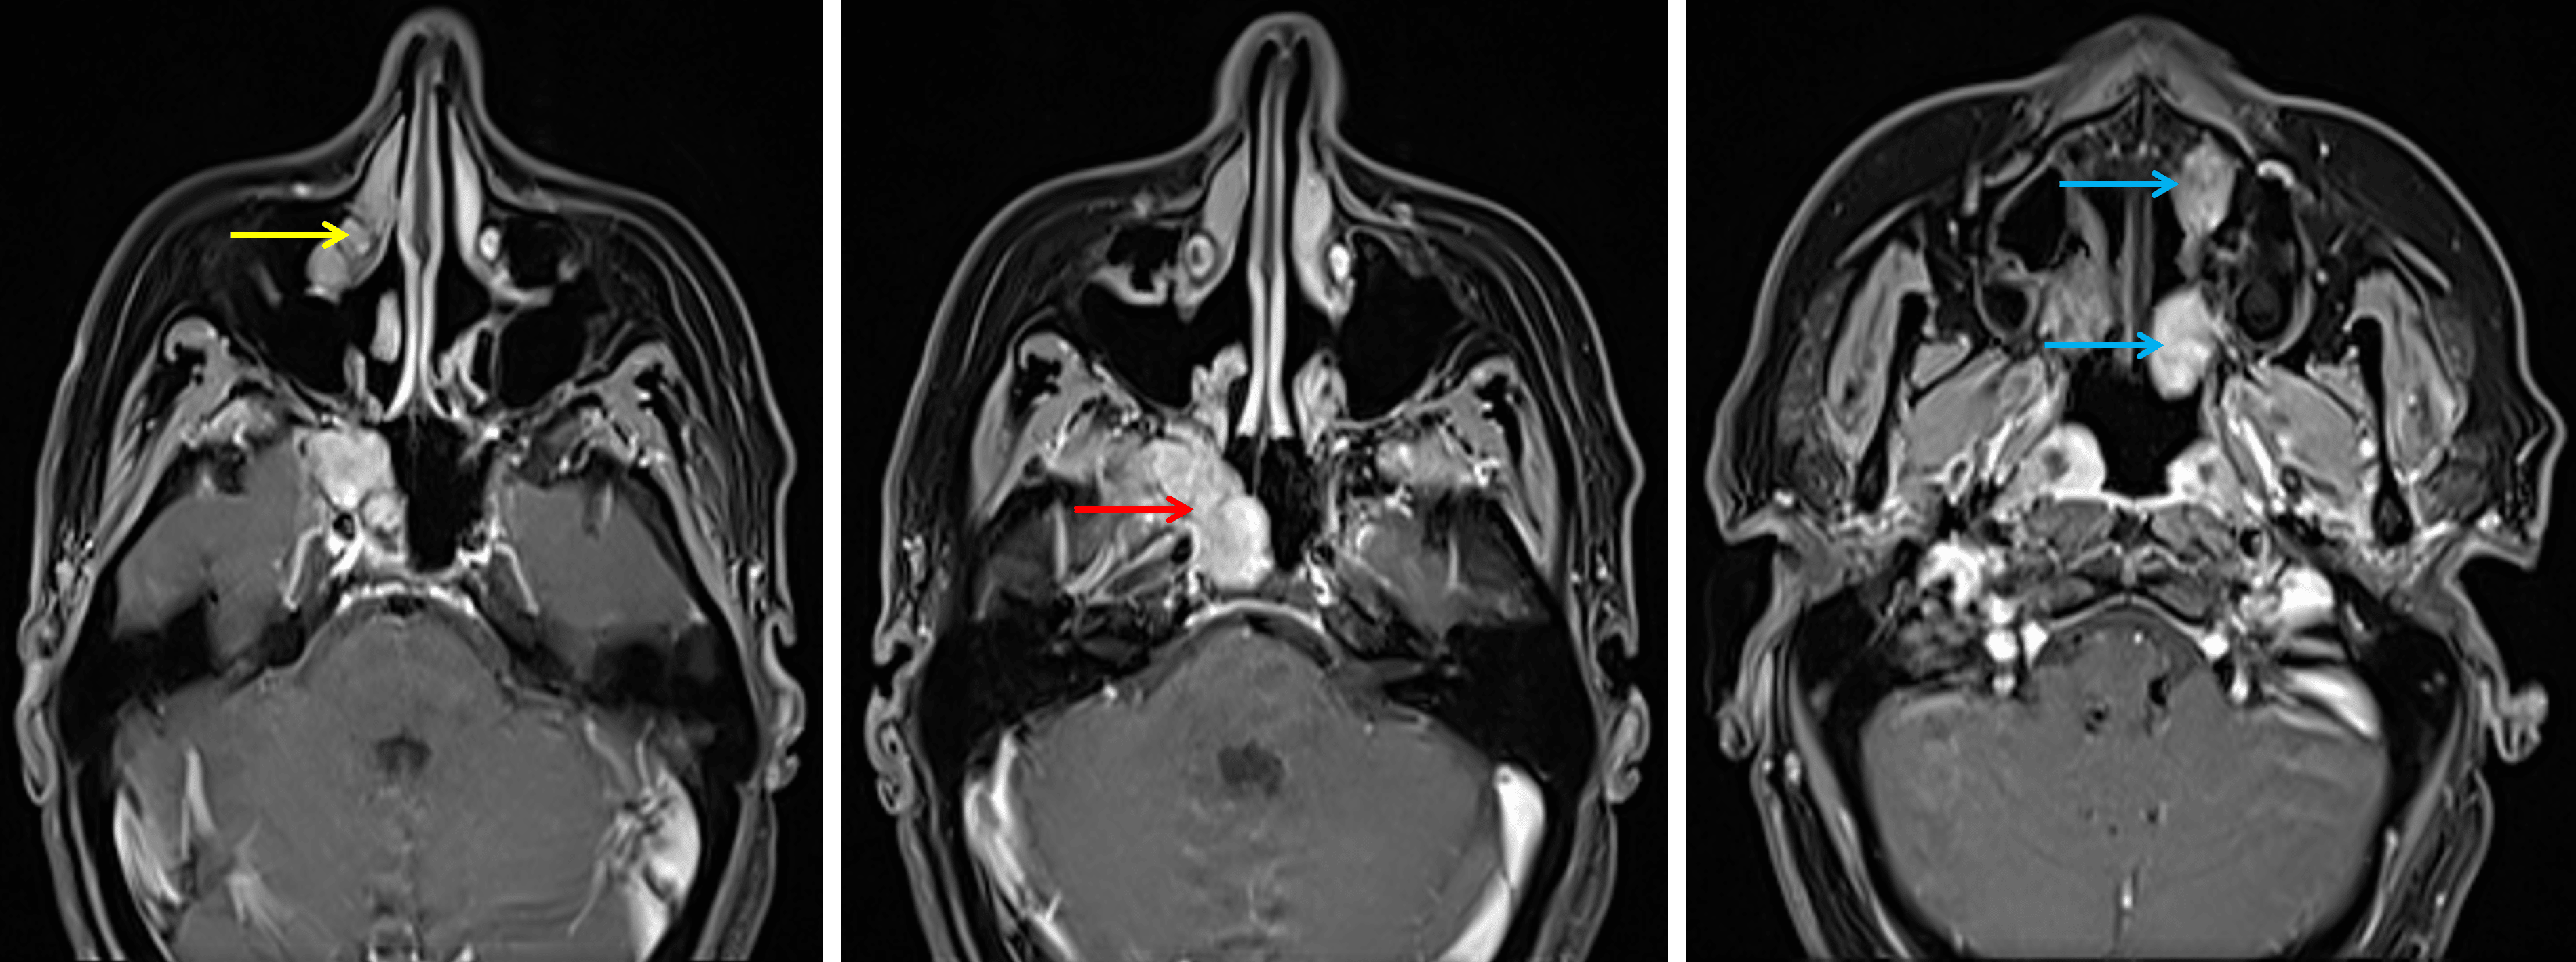

Annotated Images & Illustrations

Multiple enhancing mass involving the right skull base (red arrow), right nasolacrimal duct (yellow arrow), and left nasal cavity (blue arrows).